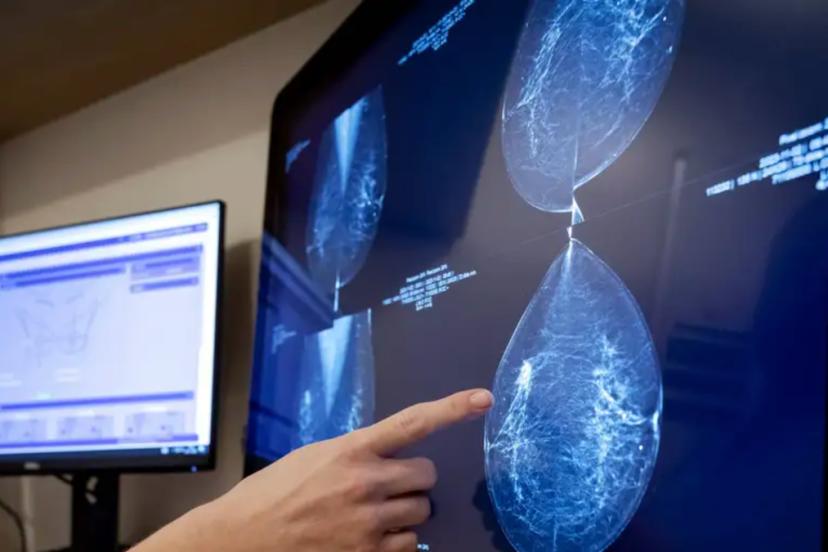

Mamografileri analiz eden yeni bir yapay zeka modeli, 5 yıla kadarki meme kanseri riskini önceden tahmin ederek erken tanı ve tedaviye olanak sağlıyor.

Meme kanseri taramasında devrim yapabilecek bir algoritma sayesinde yeni bir yapay zeka modeli, kişinin 5 yıla kadarki sürede meme kanserine yakalanma riskini başarılı şekilde ölçebiliyor.

Kanser belirtisi göstermeyen, doktorlara göre tamamen normal olan mamografi görüntülerini inceleyen model, gelecek 5 yıl için ayrıntılı bir risk ölçütü ortaya koyabiliyor.